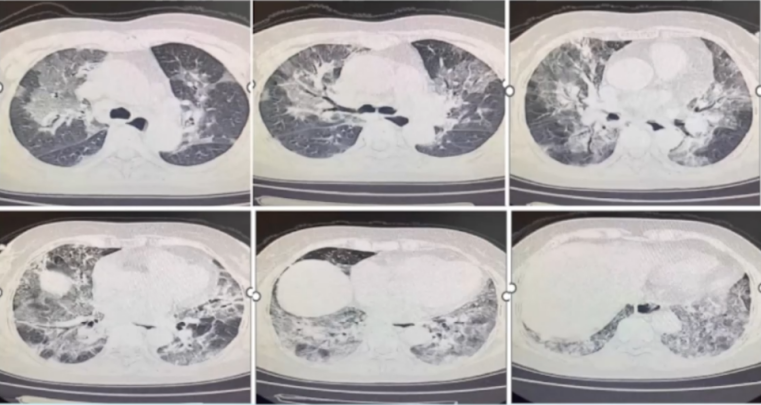

患者出院2周门诊复诊,气喘减轻,血常规、生化均未见明显异常。胸部CT:两肺磨玻璃影较前明显吸收(图6)

图片

6  随访胸部CT

2023年4月4日复查胸部CT:两肺渗出大部分吸收(图7)

7  患者胸部CT变化